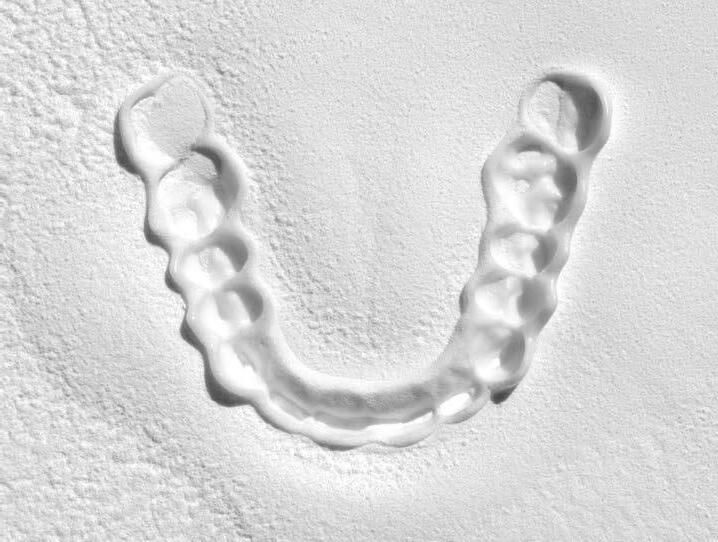

Férula de Descarga Digital de Nylon

La primera Férula de Descarga para tratar a pacientes con bruxismo y problemas de la ATM utilizando la tecnología más avanzada en impresión 3D.

Tecnología CAD/CAM para una óptima precisión y adaptación de la férula

Fabricada en Poliamida 12 con certificado en biocompatibilidad Clase IIa

Ligera, cómoda y con una alta resistencia al desgaste y a las fuerzas de la boca

(+34) 952 212 174info@ortoplus.eswww.ortoplus.es atm.ortoplus.es

Escanea el código QR para descargar el catálogo completo